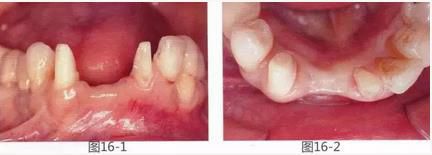

圖19-7  將非吸收性覆膜放置于黃金框架和骨移植材料上,并使用釘子固定。

圖19-8  GBR后1個(gè)月將覆膜以及黃金框架去除,這時(shí)的咬合面照。